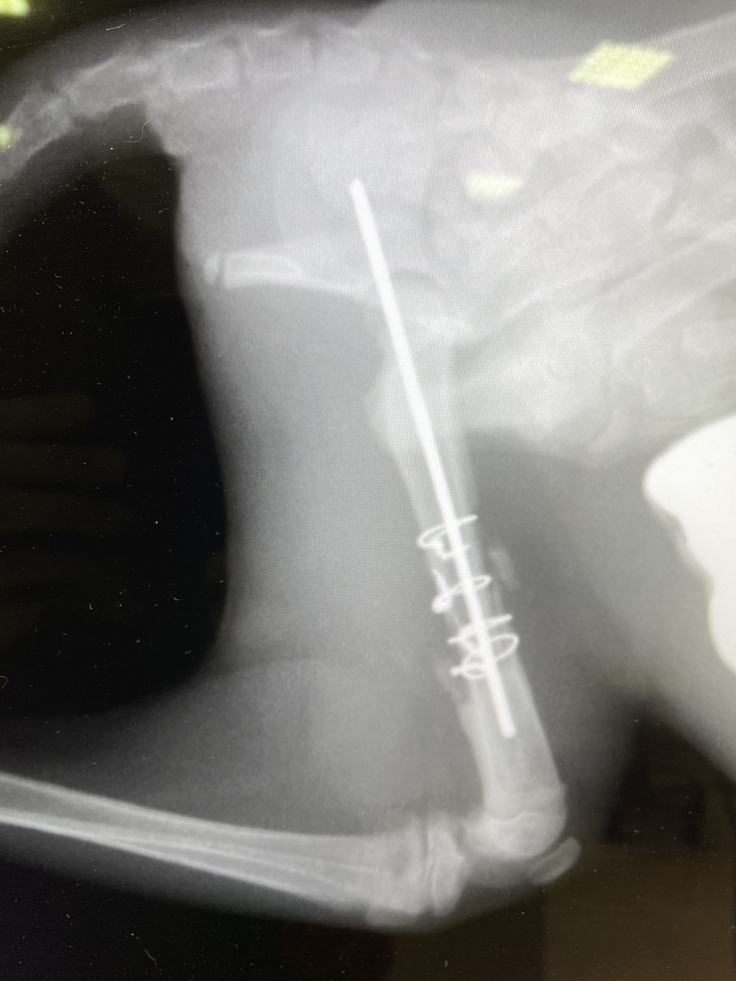

健康診断や血液検査、駆虫剤投与、レントゲン撮影などを行いました。

レントゲンの結果、左後脚大腿骨が3つに分かれていました。普通の骨折ではなく、粉砕骨折を患い、また腰骨も負傷している可能性があり、4本の足で立つことすら難しい状態でした。左後脚は力が入らず、ぶら下がってました。左後脚は手術が必要とのことで、すぐ手術の段取りをしました。

②手術&退院(8月20日〜8月21日)

8月20日に無事に手術が終わり、8月21日に退院しました。ステンレスのピンとワイヤーで骨を固定しています。服薬は難しいとのことで2週間効果が続く抗生剤の注射を退院時に接種しています。

↓[8月31日撮影]